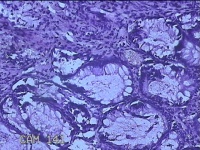

性别

男

年龄

40岁

临床诊断

混合痔

一般病史

反复肛门肿物突出15年。

标本名称

肛门肿物

大体所见

灰白暗红色肿物0.7x0.5x0.2cm一个,表面糜烂。

脱水、透明,浸蜡、脱蜡效果不佳,制片质量差。